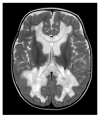

Coenzyme Q10 (CoQ10) is an endogenously synthesized lipid molecule. It is best known for its role as a cofactor within the mitochondrial respiratory chain where it functions in electron transfer and ATP synthesis. However, there are many other cellular pathways that also depend on the CoQ10 supply (redox homeostasis, ferroptosis and sulfide oxidation). The CoQ10 biosynthesis pathway consists of several enzymes, which are encoded by the nuclear DNA. The majority of these enzymes are responsible for modifications of the CoQ-head group (benzoquinone ring). Only three enzymes (PDSS1, PDSS2 and COQ2) are required for assembly and attachment of the polyisoprenoid side chain. The head-modifying enzymes may assemble into resolvable domains, representing COQ complexes. During the last two decades, numerous inborn errors in CoQ10 biosynthesis enzymes have been identified. Thus far, 11 disease genes are known (PDSS1, PDSS2, COQ2, COQ4, COQ5, COQ6, COQ7, COQ8A, COQ8B, COQ9 and HPDL). Disease onset is highly variable and ranges from the neonatal period to late adulthood. CoQ10 deficiency exerts detrimental effects on the nervous system. Potential consequences are neuronal death, neuroinflammation and cerebral gliosis. Clinical features include encephalopathy, regression, movement disorders, epilepsy and intellectual disability. Brain magnetic resonance imaging (MRI) is the most important tool for diagnostic evaluation of neurological damage in individuals with CoQ10 deficiency. However, due to the rarity of the different gene defects, information on disease manifestations within the central nervous system is scarce. This review aims to provide an overview of brain MRI patterns observed in primary CoQ10 biosynthesis disorders and to highlight disease-specific findings.